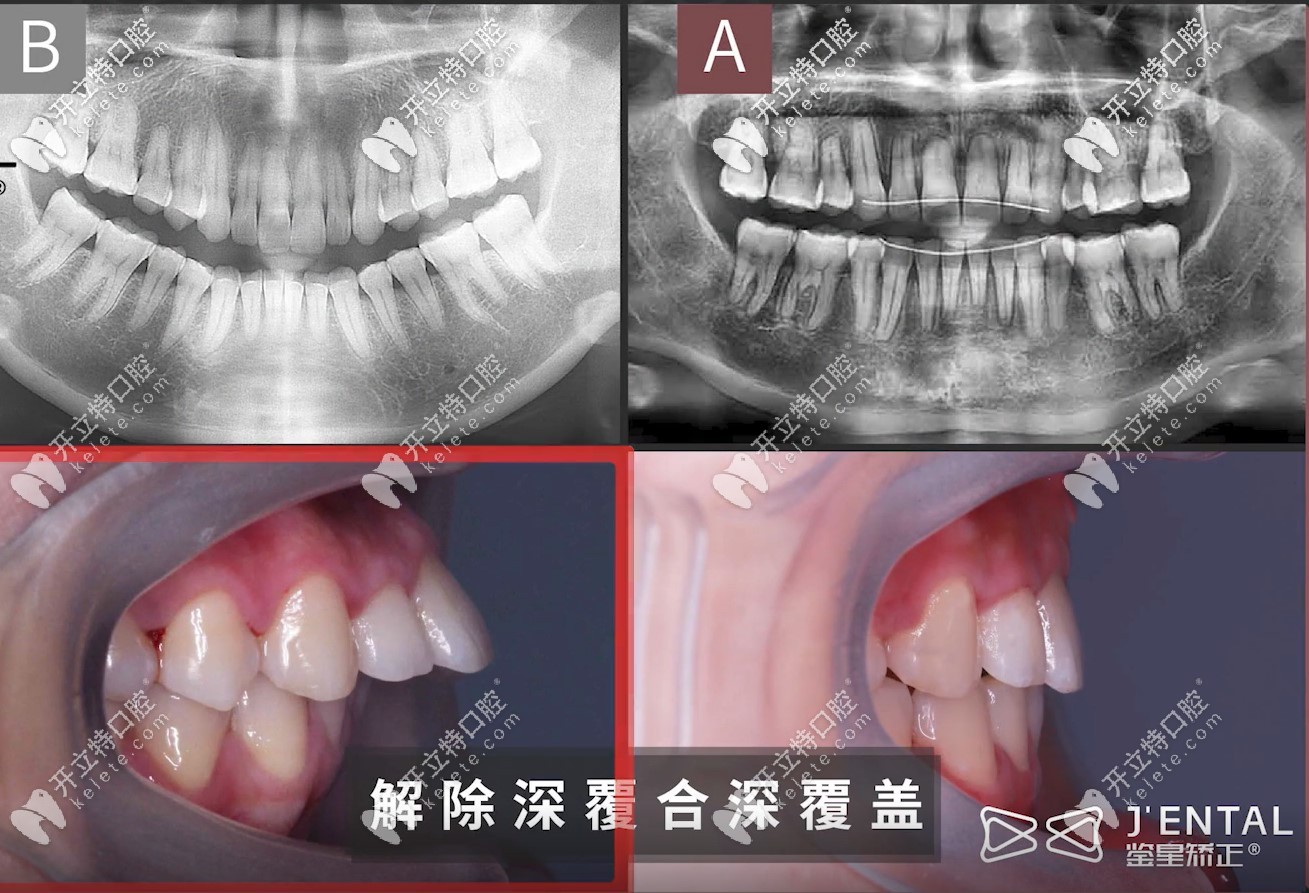

骨性深覆蓋+深覆合的小姐姐,外加露齦笑,矯正難度是非常大,在矯正過程中,為了內(nèi)收前牙,醫(yī)生打了很多的骨釘,耗費(fèi)3年時(shí)間,不僅解決了10個(gè)毫米的露齦笑問題,牙齒還內(nèi)收了7mm左右哦!

從這張圖,可以明顯看出,牙齒內(nèi)收的尺度相對(duì)比來說還是比較大滴↓↓↓

牙齒內(nèi)收7mm,順便解決了10mm的露齦笑